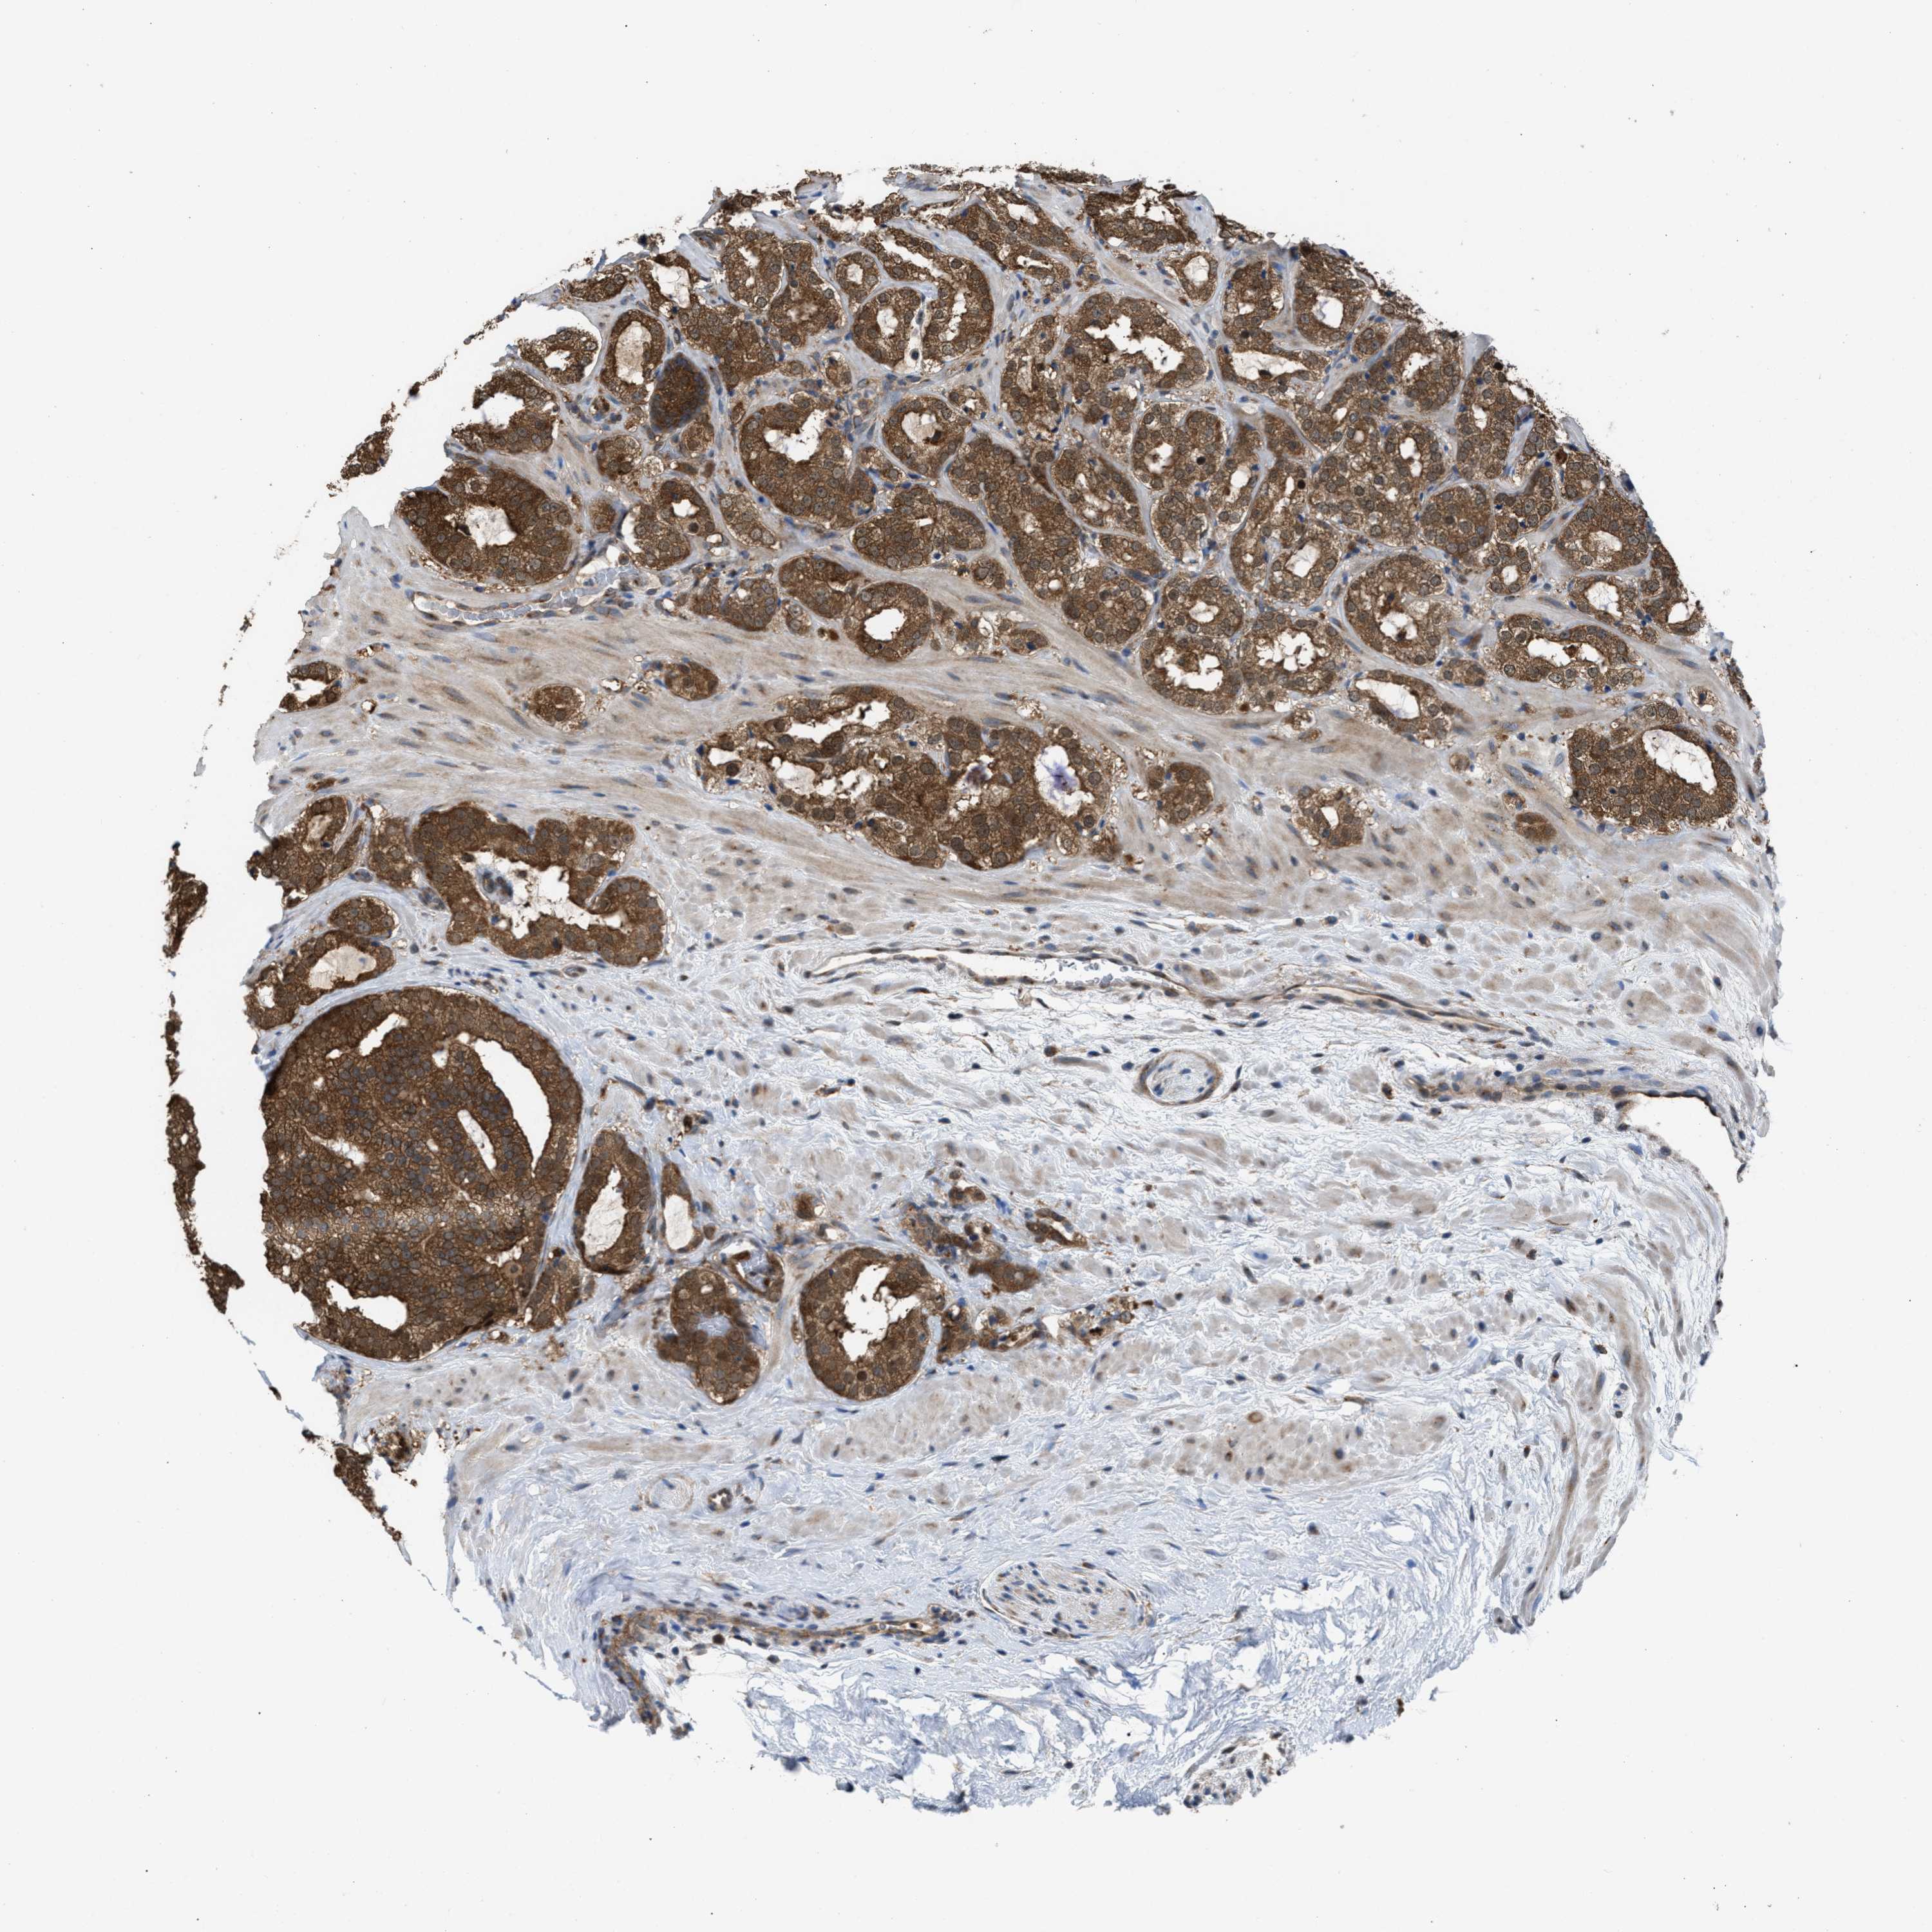

PROSTATE CANCER - Protein expressioni

A mouse-over function shows sample information and annotation data. Click on an image to view it in a full screen mode. Samples can be filtered based on level of antibody staining by selecting one or several of the following categories: high, medium, low and not detected. The assay and annotation is described here.

Antibody stainingi

Antibody staining in the annotated cell types in the current human tissue is reported as not detected, low, medium, or high, based on conventional immunohistochemistry profiling in selected tissues. This score is based on the combination of the staining intensity and fraction of stained cells.

Each image is clickable and will lead to virtual microscopy that enables deeper exploration of all samples and also displays staining intensity scores, fraction scores and subcellular localization as well as patient and tissue information for each sample.

Antibody HPA021197

Staining

High

Medium

Low

Not detected

Intensity

Strong

Moderate

Weak

Negative

Quantity

>75%

75%-25%

<25%

None

Location

Nuclear

Cytoplasmic/membranous

Cytoplasmic/membranous,nuclear

Adenocarcinoma, High grade

Adenocarcinoma, Low grade